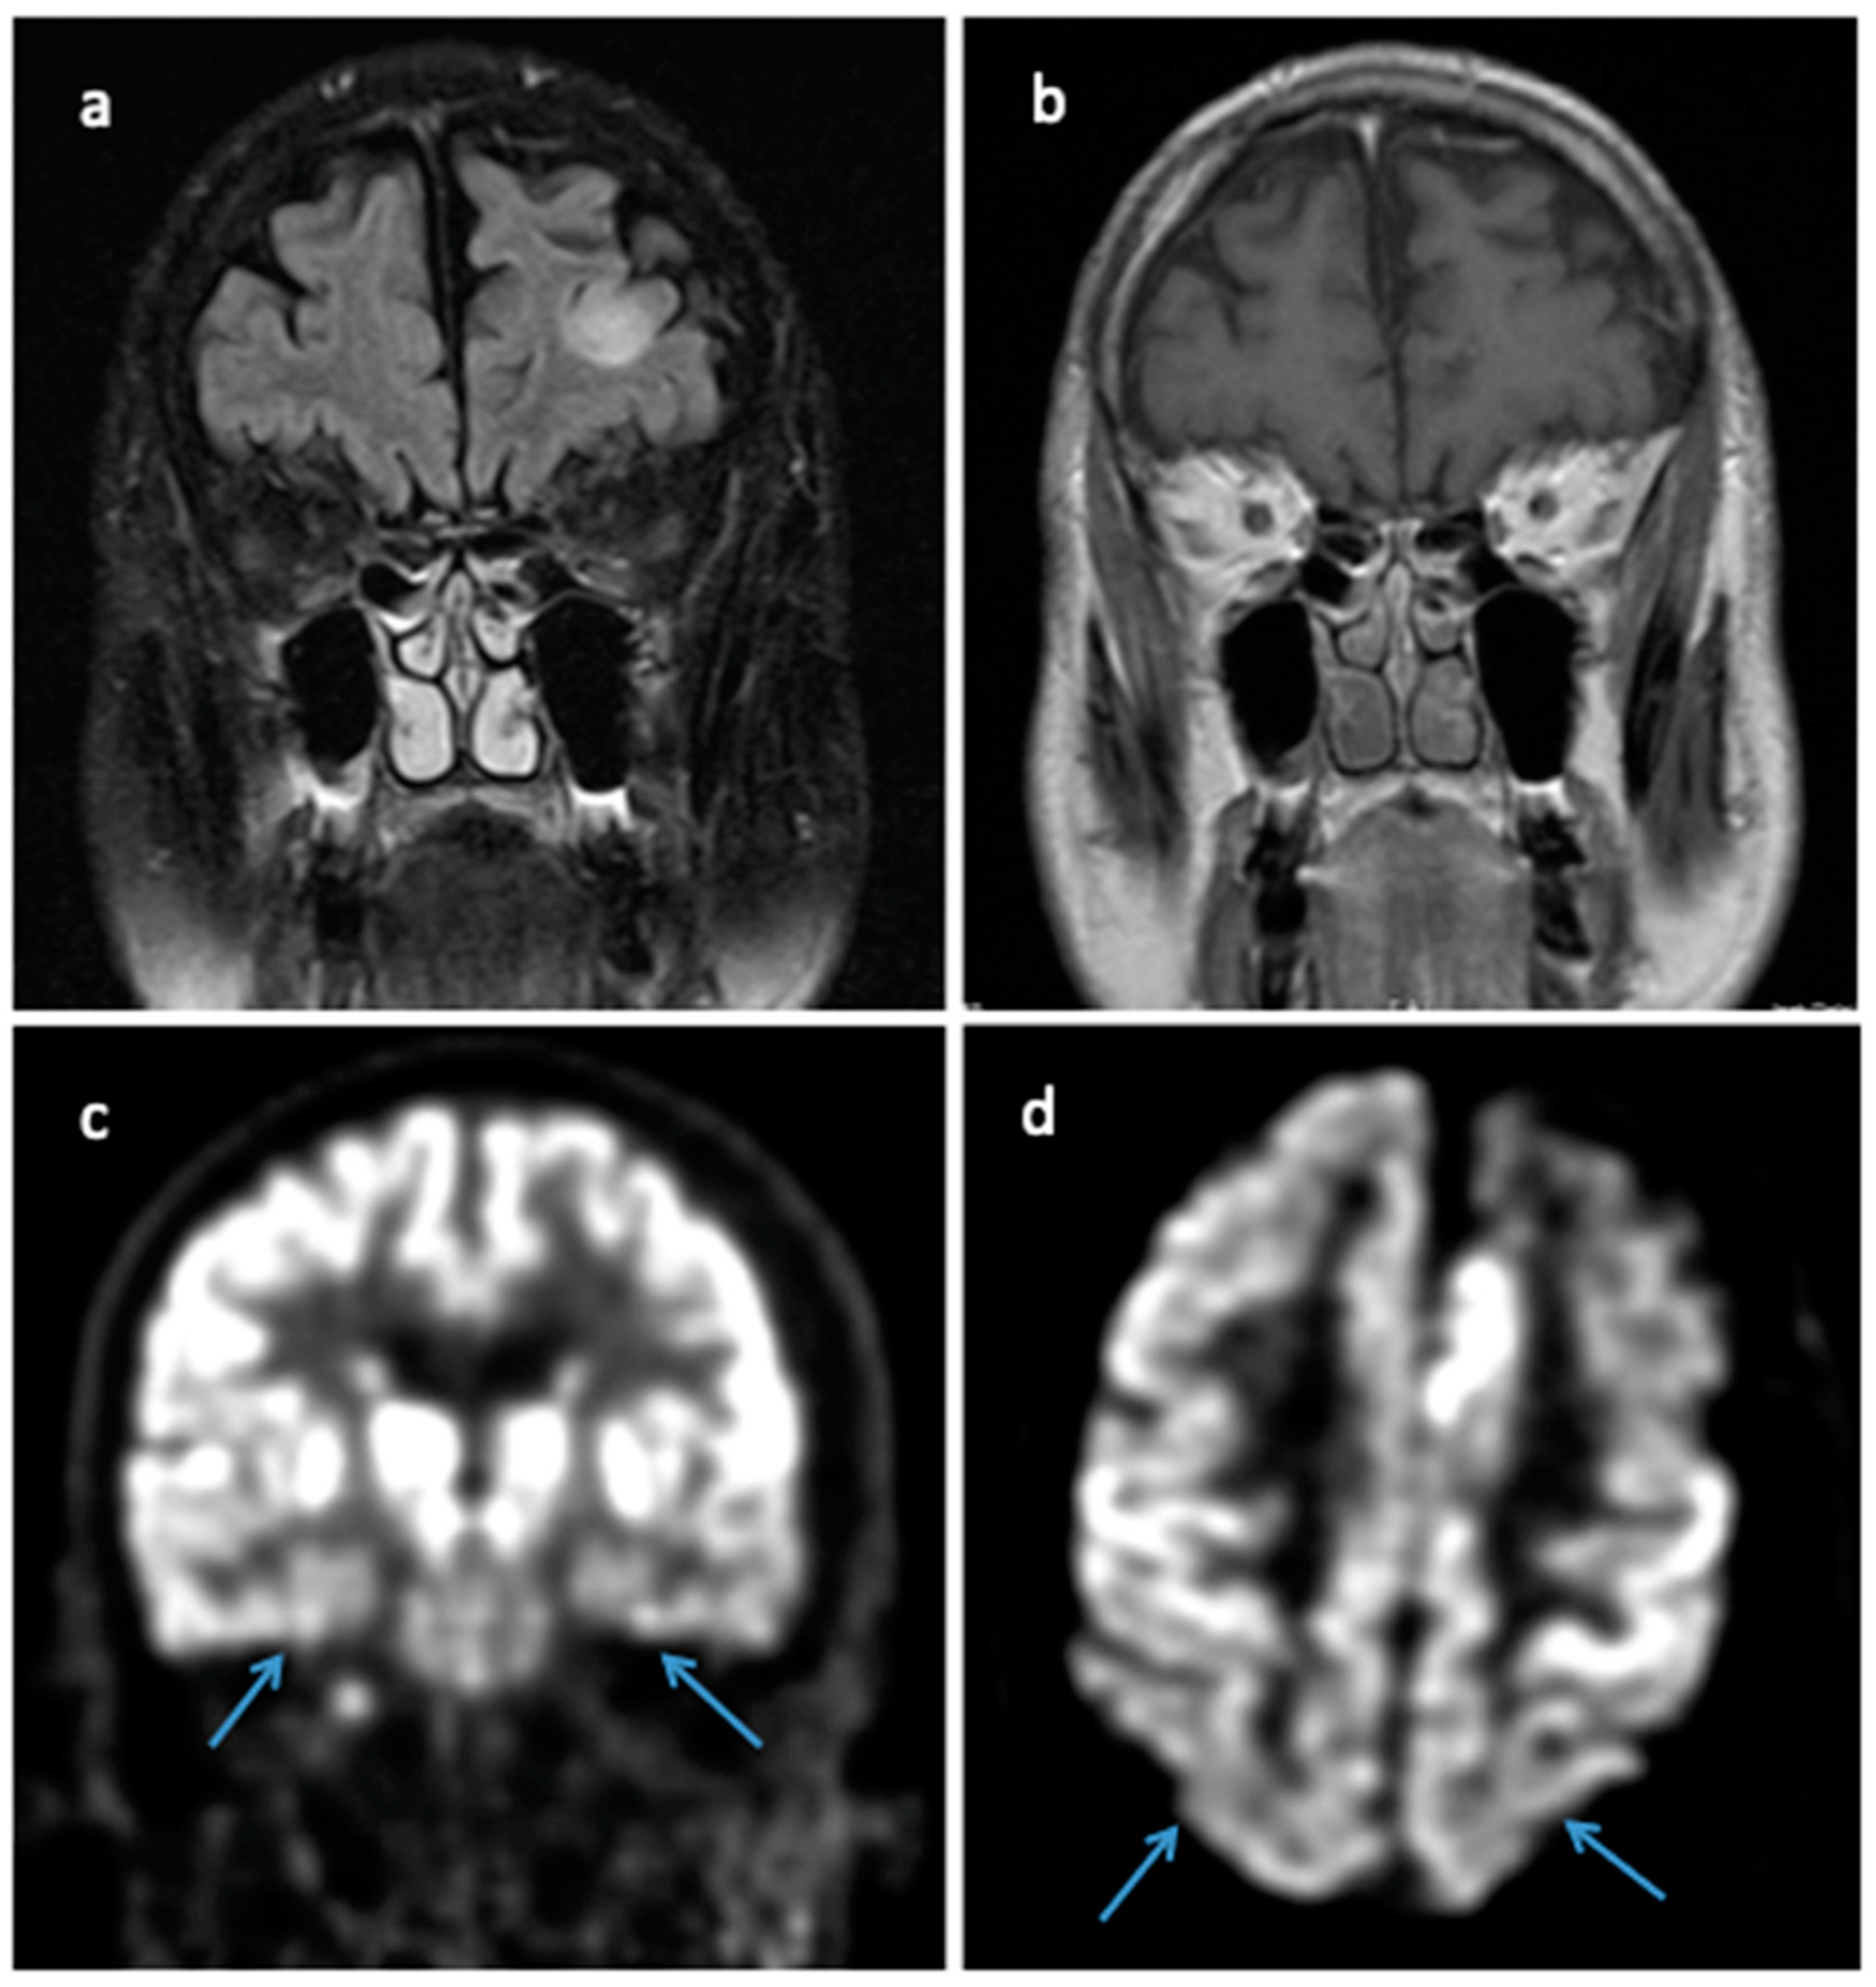

A 69-year-old male presented with a steep decline in short-term memory and difficulty maintaining attention. The patient had a family history of dementia (father in late 50s and sister at age 60). Given his cognitive decline, his primary care physician initiated donepezil and memantine and ordered MRI brain, which showed diffuse atrophy with a non-contrast enhancing, T2/FLAIR hyperintense lesion in the left frontal lobe. This lesion persisted on a follow-up brain MRI one month later (Figure 3a,b). The patent underwent a biopsy of the left frontal lesion, which showed histopathologic evidence of an astrocytic glioma IDH-wildtype and TERT promoter mutation; a significant abundance of amyloid-β plaques and tau protein was also present within this biopsy specimen.

The resected specimen revealed cortical plaques with positivity for beta-amyloid precursor protein (APP) and positive tau staining in neurons and plaques (Figure 2e,f). Of note, this patient also was diagnosed with a molecular GBM but initially presented with a non-enhancing lesion on MRI. At his initial clinic visit, an additional Montreal Cognitive Assessment screen resulted in a 10/30 score, indicating severe executive and memory function deficits. An F-18 FDG brain PET scan demonstrated hypometabolism in the bilateral temporal lobes and, to a lesser extent, in the bilateral parietal lobes (Figure 3c,d). Formal neurocognitive testing revealed cognitive deficits in all modalities tested, but no significant behavioral, affective, or gait component was identified. The patient was ultimately diagnosed with Alzheimer’s dementia.

Figure 3. (a) Coronal MRI T2 FLAIR showing left frontal hyperintense lesion. (b) Coronal MRI T1 with gadolinium contrast without any enhancement of the left frontal lesion. (c) Coronal F-18 FDG brain PET scan demonstrating hypometabolism in bilateral temporal lobes (blue arrows). (d) Axial F-18 FDG brain PET scan revealing hypometabolism in bilateral parietal lobes (blue arrows).